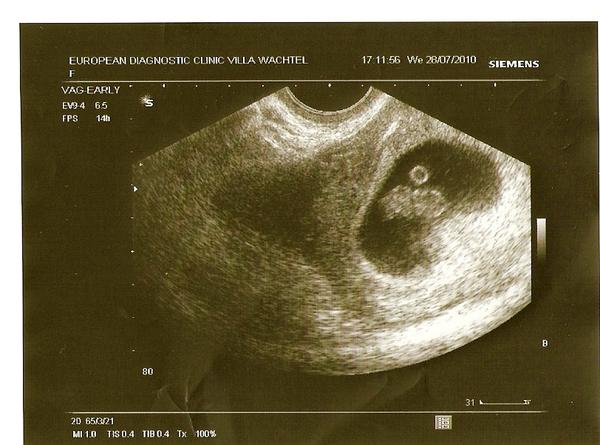

ano poprvé... viděla jsi tu fotku ??? takze jsem skoro v druhem

@monika1415 no já nevím, moc se v té fotce nevyznám. Já mám fotku s "fazolkou" už 🙂

a přidávám fotky - jedna z konce 6. týdne = 2 týdny po vynechané menstruaci, to byl vidět jen gestační váček (jako u Tebe) a pak z 9. týdne (tam je už vidět malý človíček)

no já si myslím, že dr. určil 3tt proto, že se jedná o 3tt od ovulace, tudíž jakoby správné stáří těhotenství, celkově se tedy jedná o cca 6-7tt, na uz máš krásný gestační váček uložený v děloze, zatím bez žloutkového váčku a miminka, ale to sse během týdne změní na viditelné miminko se srdíčkem🙂

Ja si myslím , že si v 7 týždni a že si to nejako blbo pochopila ten 3 tt . Odpovedalo by tomu aj foto UTZ, takže si v druhom mesiaci.